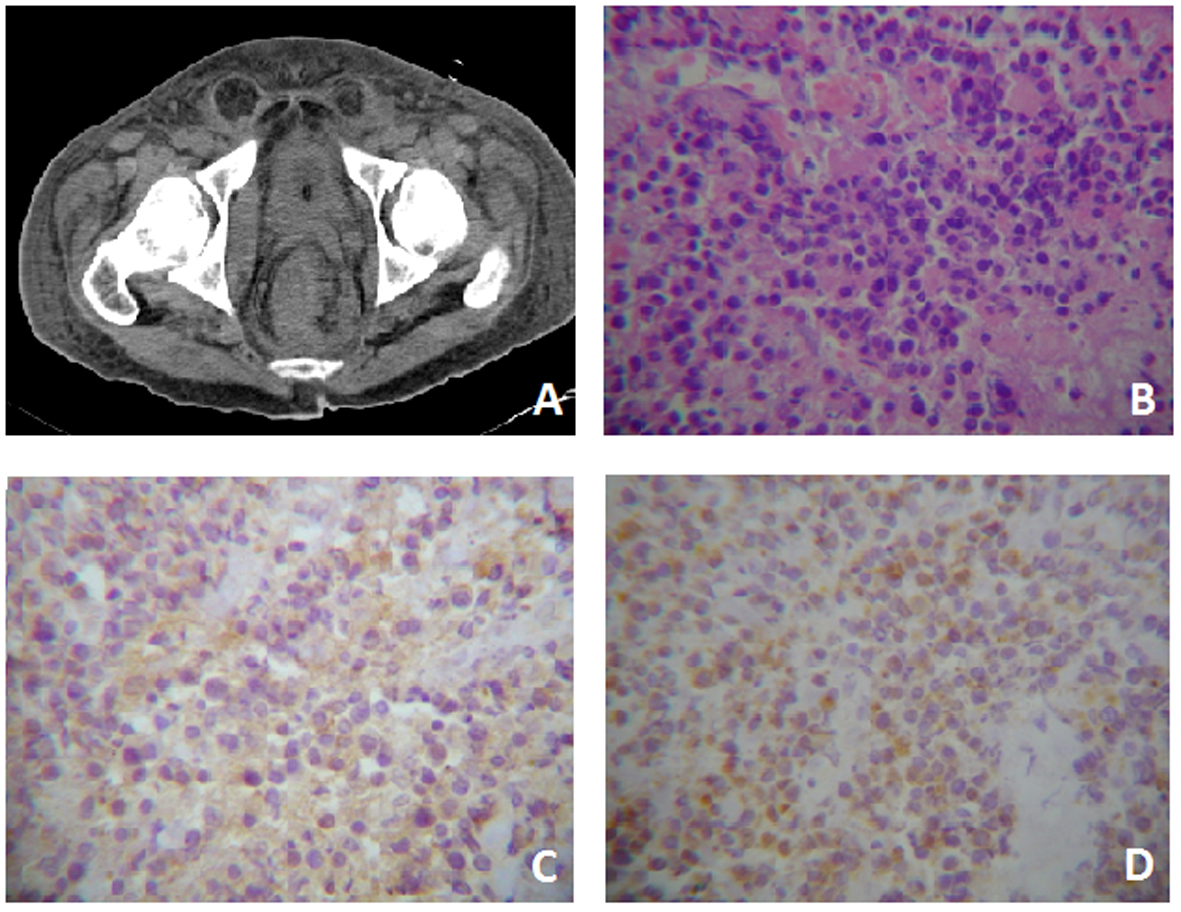

On the other hand the rectal exam showed an irregular and not actively bleeding mass in the rectal blister. Computerized Axial Tomography (CT) was performed, and the presence of a mass comprising the rectum and anus, with infiltration to the perirectal fascia and distortion of the architecture with extension to the bladder was demonstrated (Fig. 1A). Laboratory tests showed abnormal levels of lactate dehydrogenase (LDH) (561 UI/L; reference: 91 - 190 UI/L) and β-2 microglobulin (11.8 g/dl; reference: 0 - 3 g/dl).

![]() Click for large image | Figure 1. Case One. A) Pelvis CT where evidences rectal tumor with perirectal fascia engrossed. B) Tumor with extensive necrosis in the right lower quadrant, viable zones of monotonous, slightly cohesive, moderately pleomorphic plamacytoids showing a paranuclear light halo. HE (400 ×). C) Immunreactivity for CD-20 cytoplasmatic and membranous (400 ×). D) Immunohistochemistry for CD-138 membranous and cytoplasmatic (400 ×). |

Histopathological studies reported highly necrotizing neoplasia that showed a monotonous large cell pattern of lymph-shaped, eccentric nuclei, prominent nucleoli and abundant pale cytoplasm cells in its deepest portion. Immunohistochemistry showed membrane and cytoplamatic positivity to CD-20 and CD-138 and a nuclear Ki-60 on 60% of the cells (Fig. 1B-D). Bone marrow aspiration showed no evidence of tumor infiltration. A high presence of gamma serum paraprotein (37.1 g/dl; reference: 12 - 22 g/dl) was reported. The patient was treated with EPOCH-R. Nonetheless, during his hospital stay he developed a urinal tract infection that subsequently complicated as urosepsis. Urine culture revealed the presence of multi-drug resistant Pseudomonas aeruginosa and despite antimicrobial treatment the patient died.